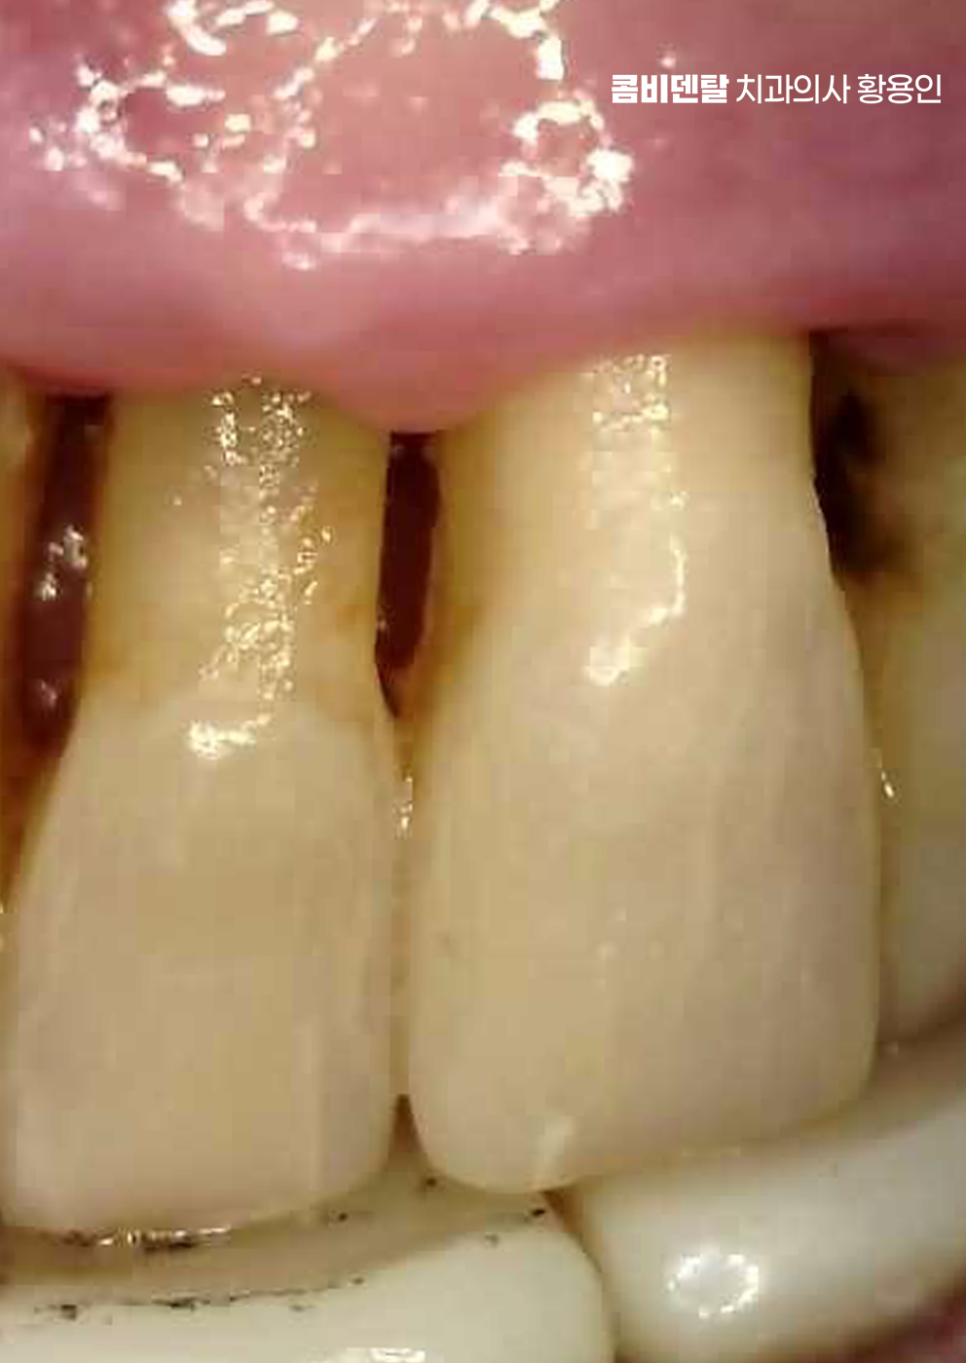

출처 아카이브 열기처음엔 그저 잇몸이 조금 붓는 정도였어요. 양치할 때 피가 나는 것도 자주 있는 일이니까 대수롭지 않게 넘겼어요, 치실을 쓰다가 피가 묻어 나오는 건 오히려 "잘 닦고 있구나" 하고 착각했어요. 그런데 어느 날부터인가 그 붓기가 자주 반복되기 시작했고, 입 안이 자꾸 텁텁하고, 입 냄새도 예전보다 쉽게 났어요, 양치를 아무리 열심히 해도 개운하지 않은 느낌이 계속됐어요. 그러면서 잇몸이 서서히 내려앉기 시작했고, 그 변화가 눈에 보이기 시작한 순간부터는 더 이상 가볍게 넘길 수 없었어요. 예전보다 치아 뿌리 쪽이 더 드러나 보이고, 잇몸선이 들쑥날쑥해지면서 거울을 볼 때마다 마음이 무거워졌어요. 크게 달라진 건 치아 사이가 눈에 띄게 벌어지기 시작했다는 거였어요.

이처럼 나이가 들수록 치아 사이 벌어짐이 잇몸이 약해지면서 더욱 심해지는 경우가 많은데 이러한 문제는 단순히 치아 배열만의 문제가 아니라 치아 수명과도 직결될 수 있는 큰 문제로도 볼 수 있는데요

또 하나 고려해야 할 부분은 치아 사이의 삼각형 공간, 즉 ‘블랙 트라이앵글’로 치주질환으로 인해 잇몸이 내려가면, 치아는 제자리에 있어도 삼각형 모양의 틈이 생기는데 이 틈은 보기에도 좋지 않을 뿐더러 음식물이 자꾸 끼는 원인이 되기도 해서 교정이나 치주치료만으로 한계가 있는 부분은 보철치료를 적절히 연계하여 치료하는 것도 경우에 따라서는 필요할 수 있어요.